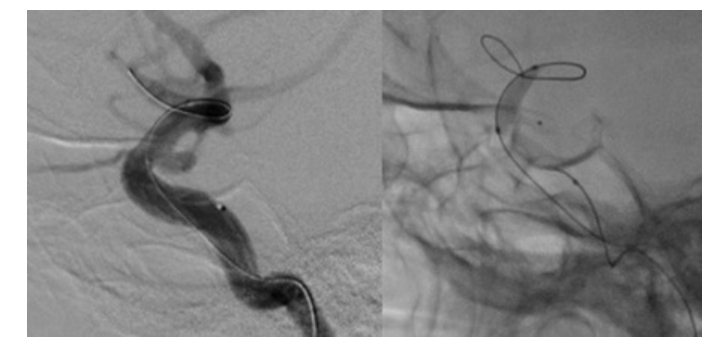

一方、②の血管内治療は、脳の血管の内側から動脈瘤にコイルをつめる手術法で、最近発展してきた技術です。細いカテーテルというチューブを動脈の内側から動脈瘤内に誘導し、細く柔らかい金属製のコイルで動脈瘤をつめます。頭を切らずに動脈瘤をつめることができることから急速に普及し始めています。不十分な閉塞に終わった症例では、瘤が再発することも報告されており、慎重な経過観察が必要となります。

治療は全身麻酔で行います。鼠径部からカテーテルという管を動脈瘤近くまで進めて留置します。そこからさらに細いマイクロカテーテルを操作して動脈瘤内に誘導、留置します。留置の際にバルーンなどの補助を使って行うこともあります。

そこからプラチナでできた柔らかいコイルを動脈瘤の中に詰めていきます。動脈瘤内にコイルが行きわたり、瘤内に血流がなくなれば手術終了です。瘤内に血流が行かなくなるので出血のリスクは格段に下がります。